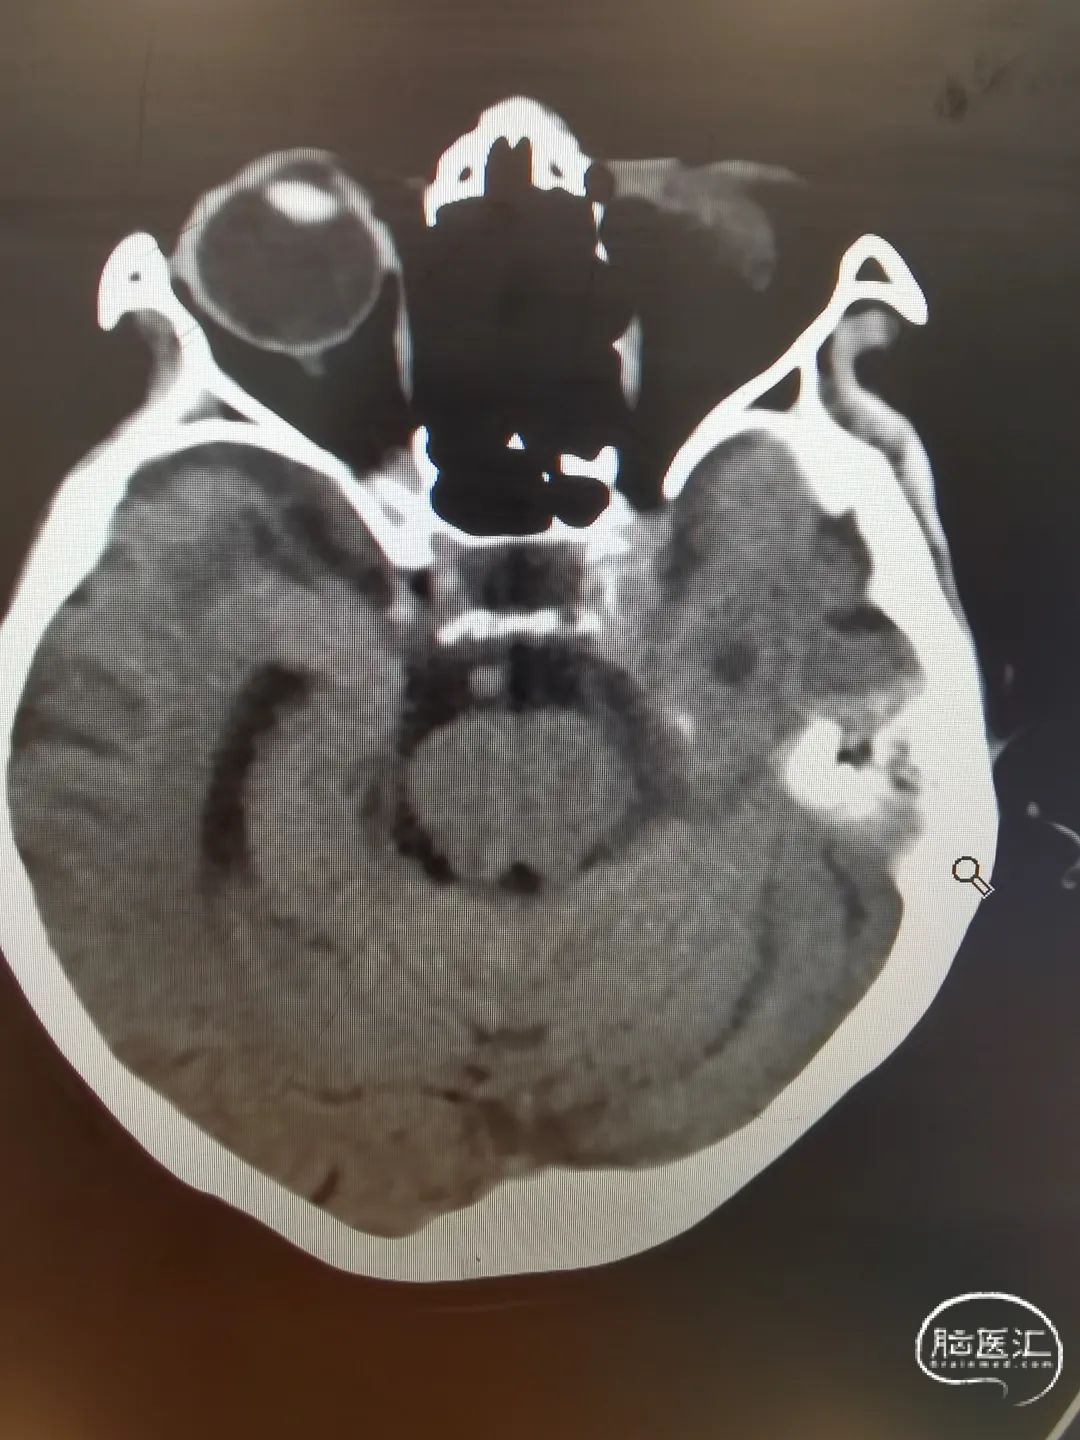

头颅CT未见明显蛛网膜下腔出血。

头颅CTA提示左侧颈内动脉迂曲,双侧血管无闭塞,大脑中动脉M1段起始处动脉瘤。

DSA造影提示主动脉III型弓,左侧颈内动脉迂曲明显,远端血管通畅。